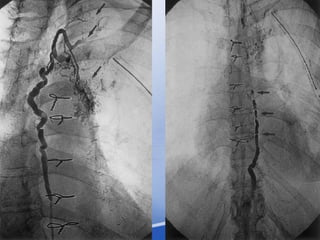

Bronchial artery embolization